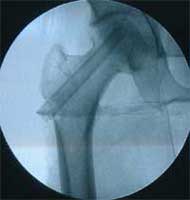

股骨头缺血性坏死MRI显示坏死区                  微创手术方法,采用隧道减压刮除死

BMP植入,异体骨支撑,恢复形态       手术后24个月X线片,关节塌陷未加重,关节功能良好,无疼痛